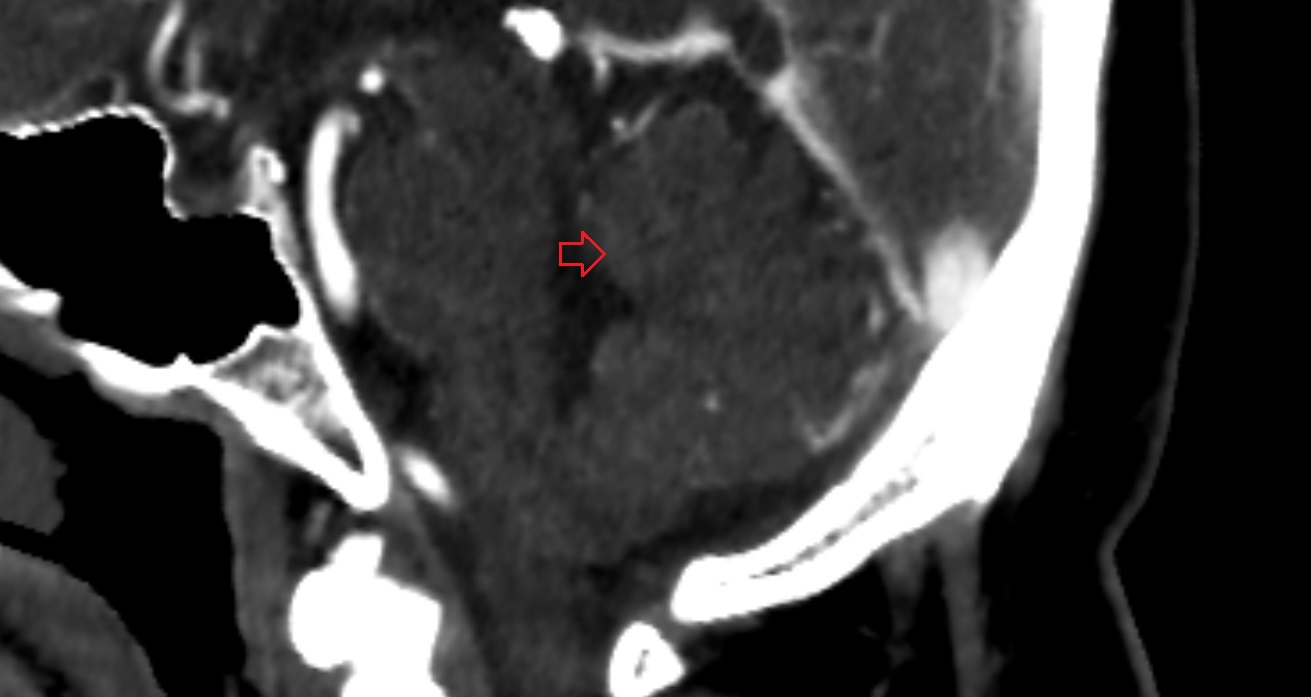

- Cerebellar tonsil (H IX)

- Tonsil of cerebellum

- Cisterna magna